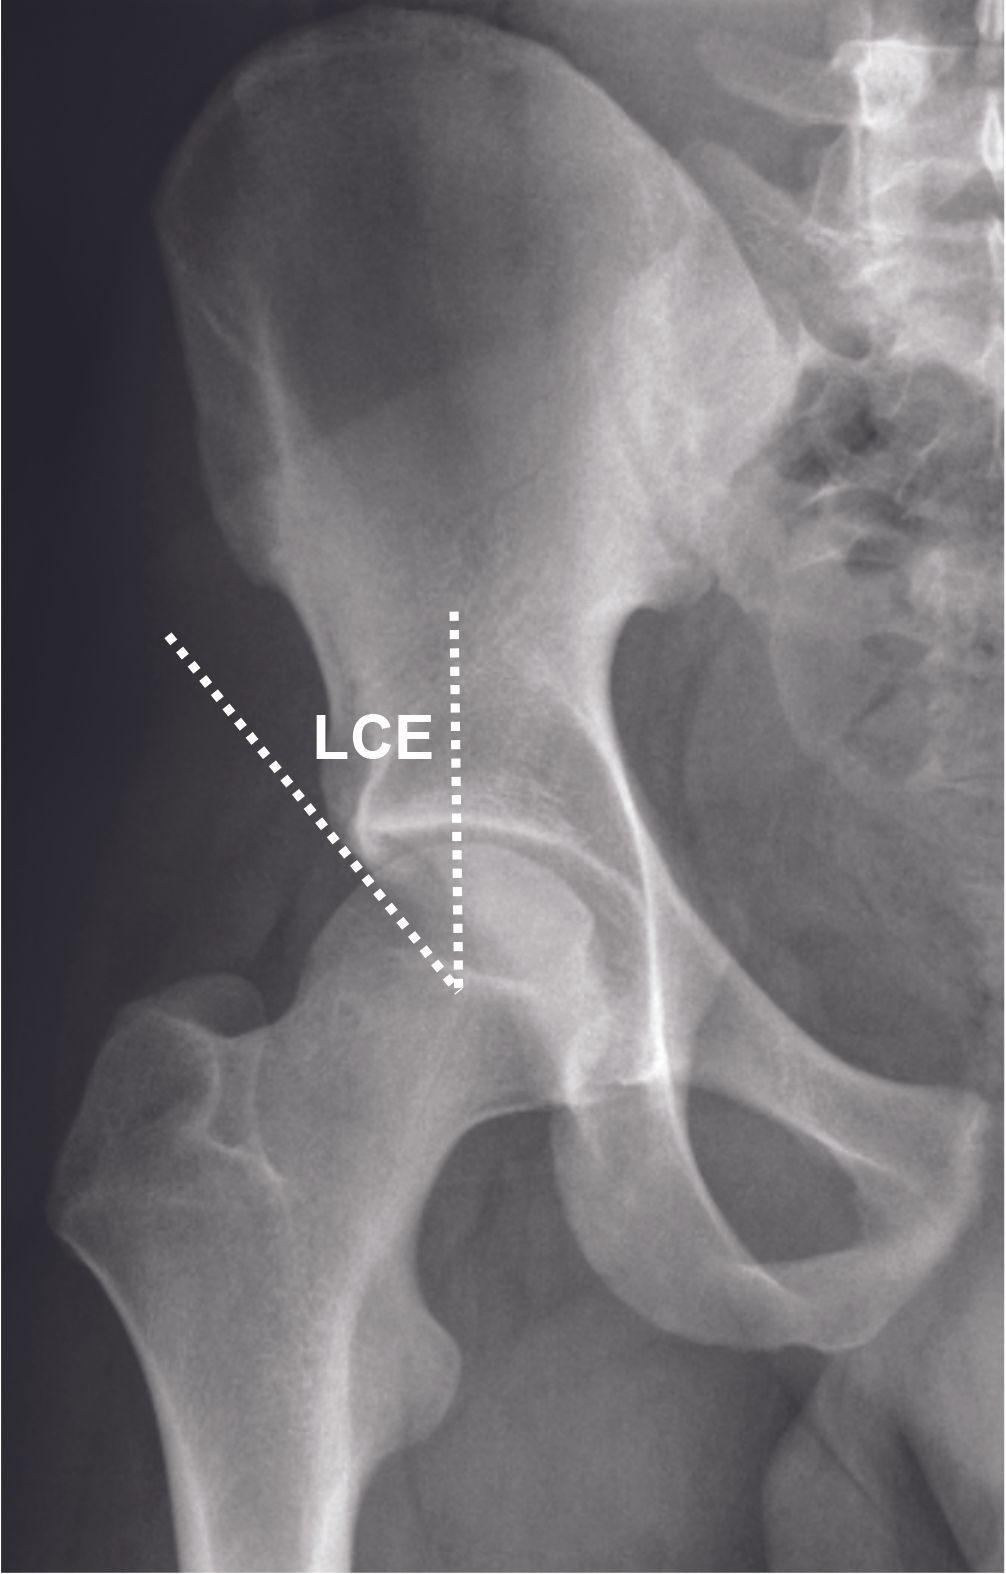

Excessive coverage of the acetabulum can lead to a pincer-type FAI. This is seen with a Wiberg Lateral Center Edge (LCE) angle greater than 33° (4) (Figure 2). Pincer-type FAI may also occur in cases of acetabular protrusion (Figure 3) when the femoral head is medial to the ilio-ischial line.